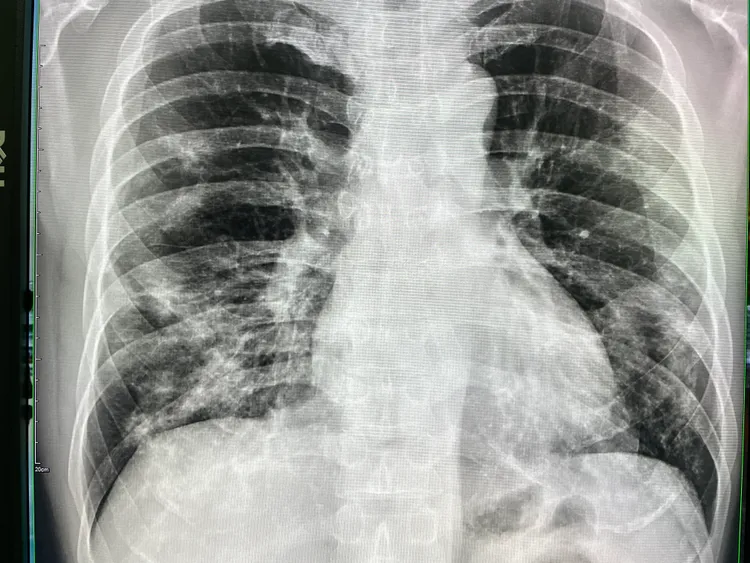

施先生肺部X光出現嚴重實質性浸潤。烏日林新醫院提供